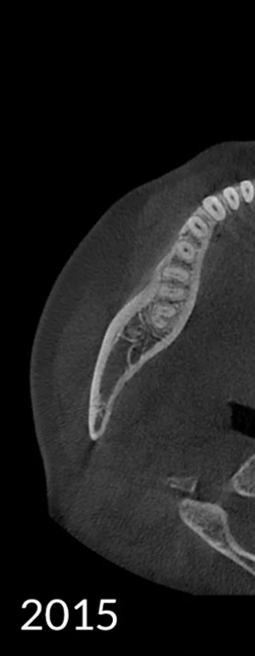

Los algoritmos matemáticos que reflejan las propiedades físicas y el avanzado motor de IA aprendido a partir de varios datos trabajan juntos para reducir el ruido y hacer que las estructuras dentales sean más claras.

Borra los artefactos metálicos y restaura con precisión las estructuras dentales, las coronas metálicas y los implantes basados en principios matemáticos.